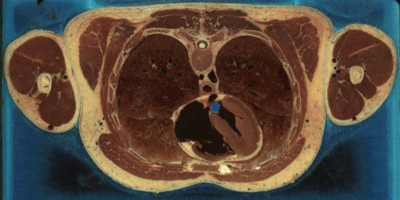

Живот.

Дело в том, что криосекция (cryosection), как сообщает словарь, — это «изготовление срезов из замороженных тканей или клеток». Иными словами, для получения требуемых изображений человеческое тело замораживается и тонко-тонко нарезается, наподобие салями. Имена людей, трупы которых шинковали исследователи из «Наглядного человека», понятное дело, не разглашаются; известно только, что это были 39-летний убийца с электрического стула и 59-летняя женщина, умершая от инфаркта. Трупы были заморожены до 85 градусов ниже нуля и, как выражаются отдельные русские эммигранты, послайсены на ломти толщиной в 1 (мужчина) и 1/3 (женщина) мм. Каждый срез аккуратно фотографировался; в результате получился 1871 снимок мужика и немного больше 5000 — тетки.